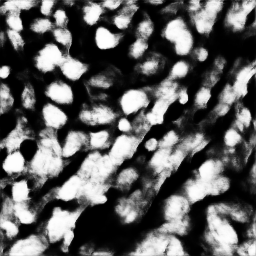

我正在研究一个二元分割问题,为了解决这个问题,我必须将细胞核从细胞中分割出来。我用二元交叉熵作为损失函数,用U-Net CNN模型.得到的图像有一些模糊的效果。我做实验的时代越多,就会越模糊。是什么导致了这样模糊的效果,我应该对我的模型做什么改变来消除它呢?

我附上了一个经过4个时代后产生的样品合成图像。